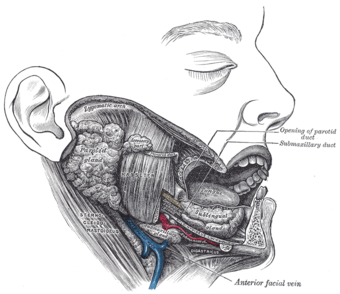

تشريح، يظهر الغدد اللعابية للجانب الأيمن. (الغدد تحت اللسانية مرئية بالقرب من أسفل اليمين.) | |

تفرز الغدة عصارتها في القنوات تحت اللسانية ، عددها من 8-20 قناة ، تفتح بمعظمها إفرادياً داخل الفم ، على قمة النتوء تحت اللساني ، و لكن بعضها قد ينضم إلى قناة الغدة تحت الفكي السفلي.

ترتوي الدم من فروع الشريانين اللساني والوجهي ، والأوردة مرافقة للشرايين وتحمل نفس الأسماء.

تتعصب الغدة تحت اللسانية من ألياف نظيرة ودية آتية أساساً من العقدة تحت الفكي السفلي. تأتي الألياف قبل العقدية من حبل الطبل فرع العصب الوجهي ( العصب القحفي السابع), وتصل العقدة عن طريق العصب اللساني فتنجز مشابك في العقدة, ثم تنضم الألياف بعد العقدية من جديد إلى العصب اللساني وذلك في طريقها إلى التوزع على الغدة . لهذه الغدة تعصيب ودي أيضاً